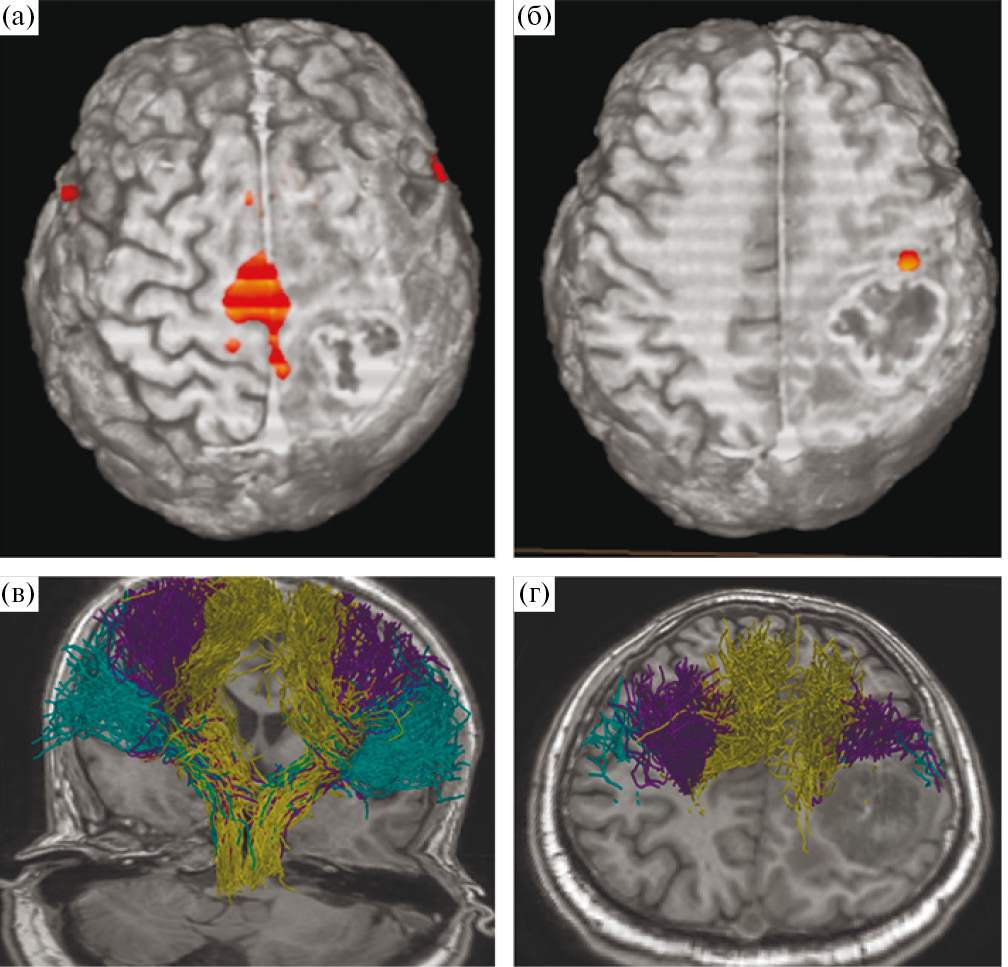

Учитывая локализацию процесса и клиническую картину заболевания, в качестве предоперационной подготовки пациенту были проведены фМРТ с визуализацией моторных зон и МР-трактография с построением КСТ (рис. 4).

Рис. 4. МРТ у пациента с внутримозговой опухолью правой теменной доли. (а, б) – данные фМРТ; (а) – оранжевым цветом обозначена корковая зона ноги, располагающаяся вовнутрь и на некотором отдалении от медиальной границы опухоли; (б) – представлена зона руки, прилегающая к переднему краю опухоли; (в, г) – данные МР-трактографии (CSD HARDI), использованный алгоритм построения позволил построить и разделить волокна КСТ, иннервирующие ногу (горчичный цвет), руку (фиолетовый), лицо (зеленый). Волокна КСТ прилегают к медиальному и переднему краям опухоли.

Fig. 4. fMRI (leg and arm areas) and MR-tractography (CSD HARDI, yellow – leg, purple – hand, green – facial muscles) before surgery.